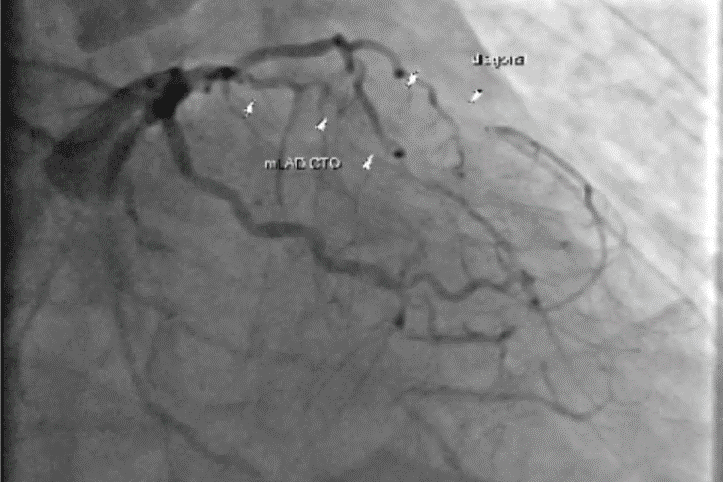

冠狀動脈

冠狀動脈狹窄

冠狀動脈阻塞

冠心症